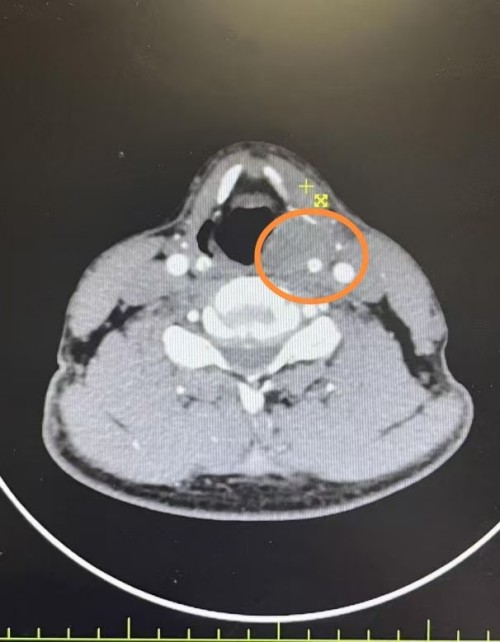

经电子鼻咽喉镜及颈部CT检查,孙先生左侧梨状窝存在菜花样新生物,且左侧声带固定,病理结果确诊为下咽癌。结合中医四诊信息,辨证属痰湿瘀阻证。考虑到患者病情复杂,若直接手术极可能导致失声,而患者有强烈的保声意愿,赵龙珠主任迅速启动了多学科会诊(MDT)。

经过一次动脉灌注化疗后,复查显示患者梨状窝肿瘤明显缩小,双侧声带活动恢复正常,成功实现肿瘤降期。

治疗前